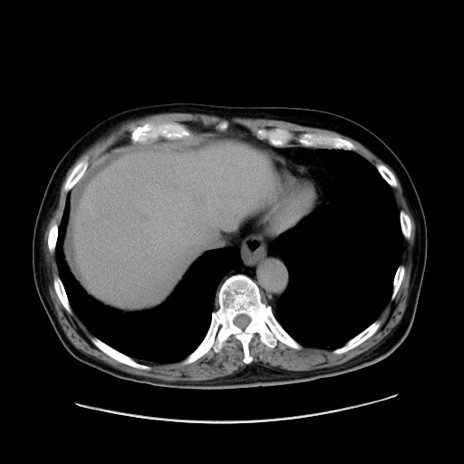

症例30(横断像)

【症例】80歳代男性

【現病歴】約6時間前から臍下部痛が出現。次第に腹部膨隆・背部痛も生じてきたため来院。背部痛の場所は変化しない。

【身体所見】意識清明、BT 36.3℃、BP  131/87mmHg、P 87bpm、SpO2 100%(RA)、臍周囲自発痛・圧痛あり、反跳痛なし、自発痛部位に一致して板状硬あり、腹部膨隆、腸雑音減弱、CVA tenderness両側陰性。